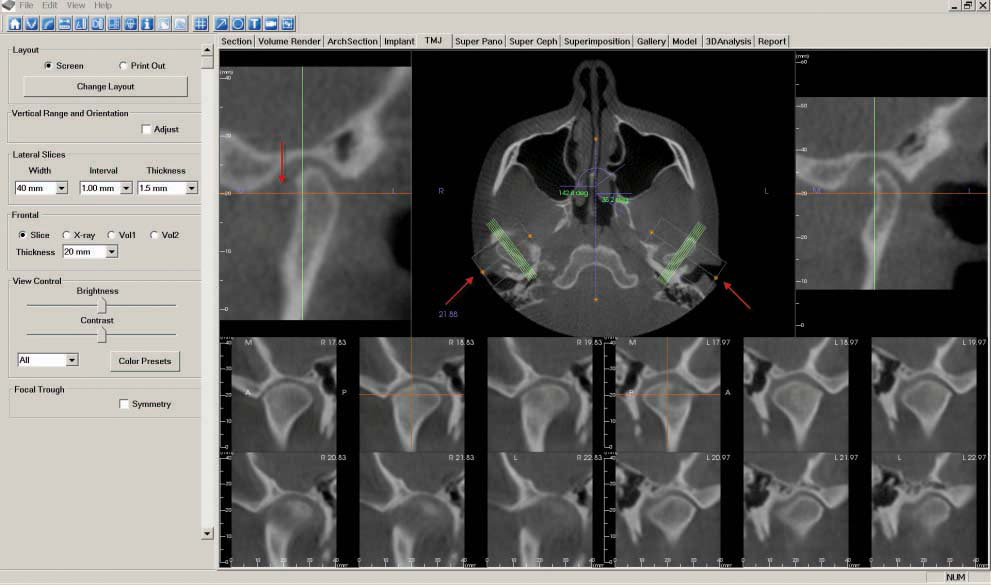

g. Next, go to the "TMJ" tab to create the "TMJ Coronal" image. First, move the orange line while focusing on the center image until the condyles (shaped like kidney beans) appear. Click on the white rectangle and position over each condyle, using the orange points to bisect the vertical center of the condyles. Rotate the boxes 90 degrees toward the midline to make coronal slices of the condyles. You can adjust the width and interval settings to ensure the slices match the size of the condyles.

As described in step 7, "Capture to Gallery" and select "Whole View" in the "Select Image to Capture" pop-up window. Click "OK," then name the image "TMJ Coronal."

h. The "TMJ" tab is also used to create the "TMJ Sagittal" image. Click on the white rectangle and position over each condyle, using the orange points to bisect the horizontal center of the condyles. Rotate the boxes toward the midline to bisect the condyle. Adjust the interval setting to view slices of the entire width of the condyles.

As described in step 7, "Capture to Gallery" and select "Whole View" in the "Select Image to Capture" pop-up window. Click "OK," then name the image "TMJ Sagittal."